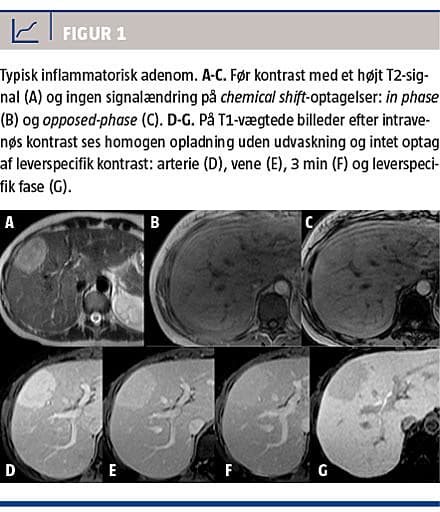

Adenomer med muteret HNF1α-gen (Figur 2) er

iso- eller lethyperintense på T2-vægtede billeder og iso- eller hyperintense på T1-vægtede billeder med diffust signaltab på chemical shift-optagelser pga. intracellulær steatose. De ses ofte i en diffust steatotisk lever og har moderat opladning i arteriefase, ingen persisterende opladning i senere faser, men vender hurtigt tilbage til udseendet før kontrastindgift [12, 22].